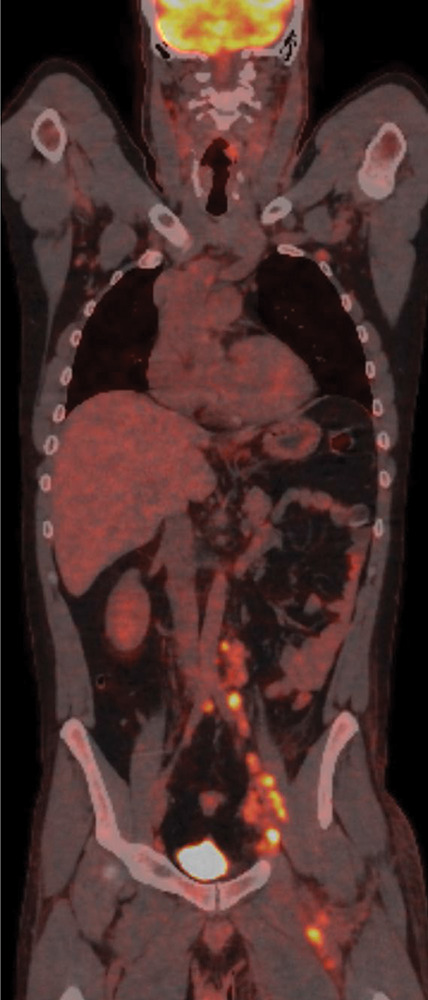

教学点:卡波西肉瘤是一种罕见的疾病,最常见于人类免疫缺陷病毒(HIV)患者、接受免疫抑制剂的患者或非洲患者。放射成像在促进诊断和随访方面发挥作用,目前主要是正电子发射断层扫描-计算机断层扫描(PET - CT)(1)。

Teaching point: Kaposi sarcoma is a rare disease most commonly occurring in patients with human immunodeficiency virus (HIV), in patients receiving immunosuppressants or in African patients. Radiological imaging has a role in facilitating the diagnosis and follow‑up, currently primarily with positron emission tomography-computed tomography (PET‑CT) (1).